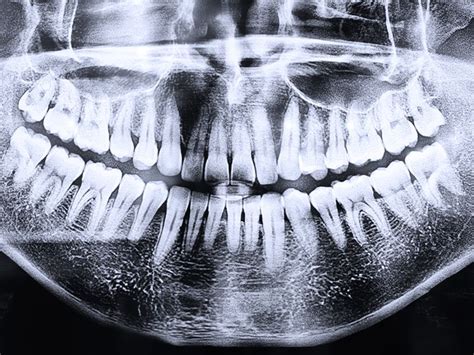

La ortopantomografía es un estudio radiológico que permite observar todos los dientes, tejidos de soporte y estructuras anatómicas adyacentes. Se trata de una imagen bidimensional de un objeto tridimensional, por lo que las imágenes pueden superponerse. Aunque es una radiografía muy útil para un diagnóstico inicial, esta superposición algunas veces impide una visualización detallada de ciertas patologías.

En una radiografía panorámica se pueden ver una infinidad de estructuras anatómicas. Para empezar, podemos ver tanto los dientes superiores como los inferiores y sus respectivas raíces. A continuación podemos ver el hueso, clave en la colocación de implantes.

A partir de aquí en la ortopantomografia se pueden ver una infinidad de estructuras anatómicas. Entre ellas encontramos:

Una de las principales ventajas de la radiografía panorámica dental es que proporciona una imagen completa de las estructuras anatómicas de la cavidad bucal y sus alrededores. Esta vista general facilita a los profesionales de la odontología evaluar y diagnosticar diversas afecciones con mayor precisión. Gracias a su capacidad para mostrar todas las estructuras anatómicas de manera integral, la radiografía panorámica dental se ha convertido en una herramienta imprescindible para evaluar la salud bucodental de los pacientes.

Visión general de la boca y los dientes. Las radiografías panorámicas proporcionan una vista completa de los dientes, las encías, los huesos y los tejidos blandos de la boca. Permiten al dentista obtener una imagen precisa de las piezas dentales y los huesos de la mandíbula. Una radiografía panorámica puede realizarse en unos pocos minutos y no requiere la toma de múltiples imágenes para obtener una visión completa de la boca y los dientes.